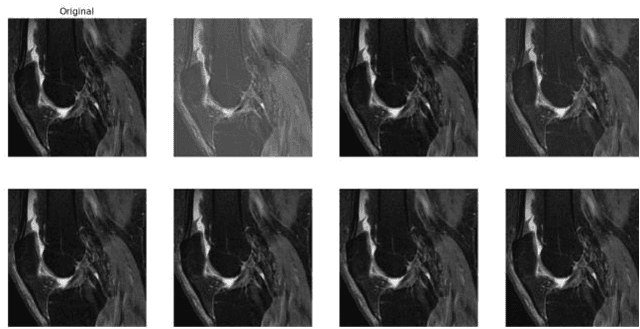

Abstract:Knee osteoarthritis (KOA) is a common joint disease that causes pain and mobility issues. While MRI-based deep learning models have demonstrated superior performance in predicting total knee replacement (TKR) and disease progression, their generalizability remains challenging, particularly when applied to imaging data from different sources. In this study, we have shown that replacing batch normalization with instance normalization, using data augmentation, and applying contrastive loss improves model generalization in a baseline deep learning model for knee osteoarthritis (KOA) prediction. We trained and evaluated our model using MRI data from the Osteoarthritis Initiative (OAI) database, considering sagittal fat-suppressed intermediate-weighted turbo spin-echo (FS-IW-TSE) images as the source domain and sagittal fat-suppressed three-dimensional (3D) dual-echo in steady state (DESS) images as the target domain. The results demonstrate a statistically significant improvement in classification accuracy across both domains, with our approach outperforming the baseline model.